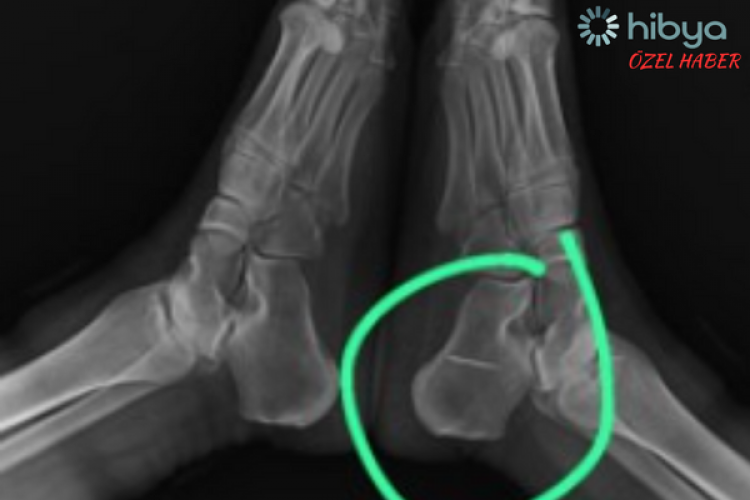

Semra S'nin (43) 10 yaşlarında, evde oynadığı sırada yere düşen dikiş iğnesi, tamamen ayağının içine girip, topuk bölgesindeki kemiğe saplandı.

Röntgen sonucunu inceleyen doktor, Semra S'nin ayağının topuk kemiğindeki dikiş iğnesini görünce gözlerine inanamadı.

Hastasına bilgi vermesinin ardından, iğnenin kemiğe saplandığını ve hareket etmediği belirleyen acil servis hekimi, herhangi bir işlem yapılmasa da söz konusu iğnenin sorun yaratmayacağını iletti.